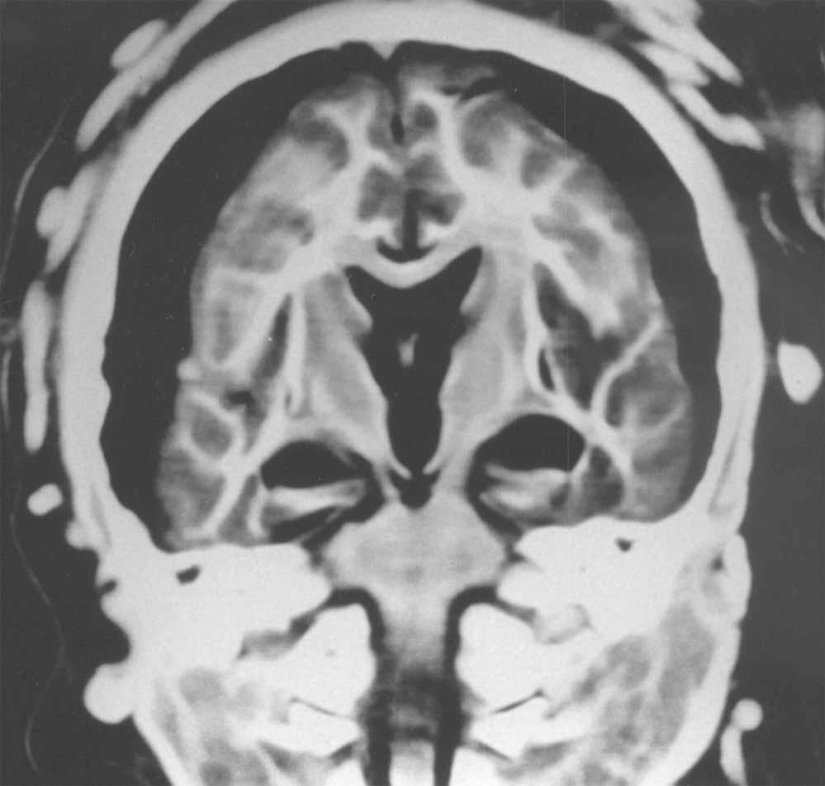

Y esta radiografía mostró que el cerebro de un niño de 5 años estaba preservado en perfectas condiciones.